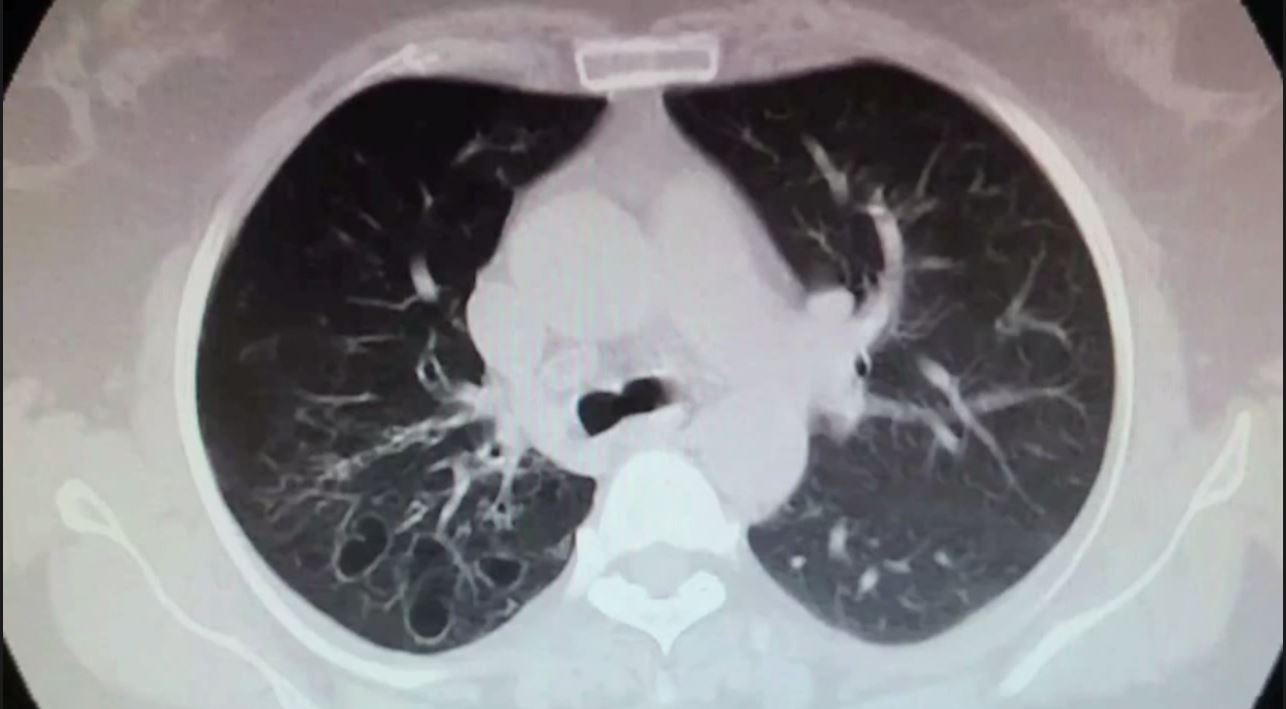

This week on The Beat, CTSNet Editor-in-Chief Joel Dunning spoke with Dr. Michael Lanuti, Director of Thoracic Oncology in the Division of Thoracic Surgery at Massachusetts General Hospital and an Associate Professor at Harvard Medical School, and thoracic surgeon and CTSNet Senior Editor Leanne Ashrafian about Dr. Lanuti’s thoughts on the JCOG0802 trial and how he believes the wrong parameters were measured. They discussed local recurrence rates, pulmonary function, and the subtypes of adenocarcinoma. Additionally, they explored how to apply these results to future patients, central and peripheral lesions, and other randomized trials. They also covered the five-year results of the JCOG0802 trial and future studies and the implications for future studies, focusing on the parameters that should be considered. Furthermore, they addressed pulmonary function tests and wedge resection.